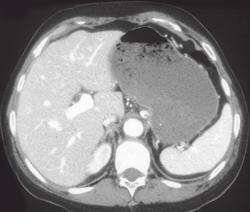

Gastric Adenocarcinoma